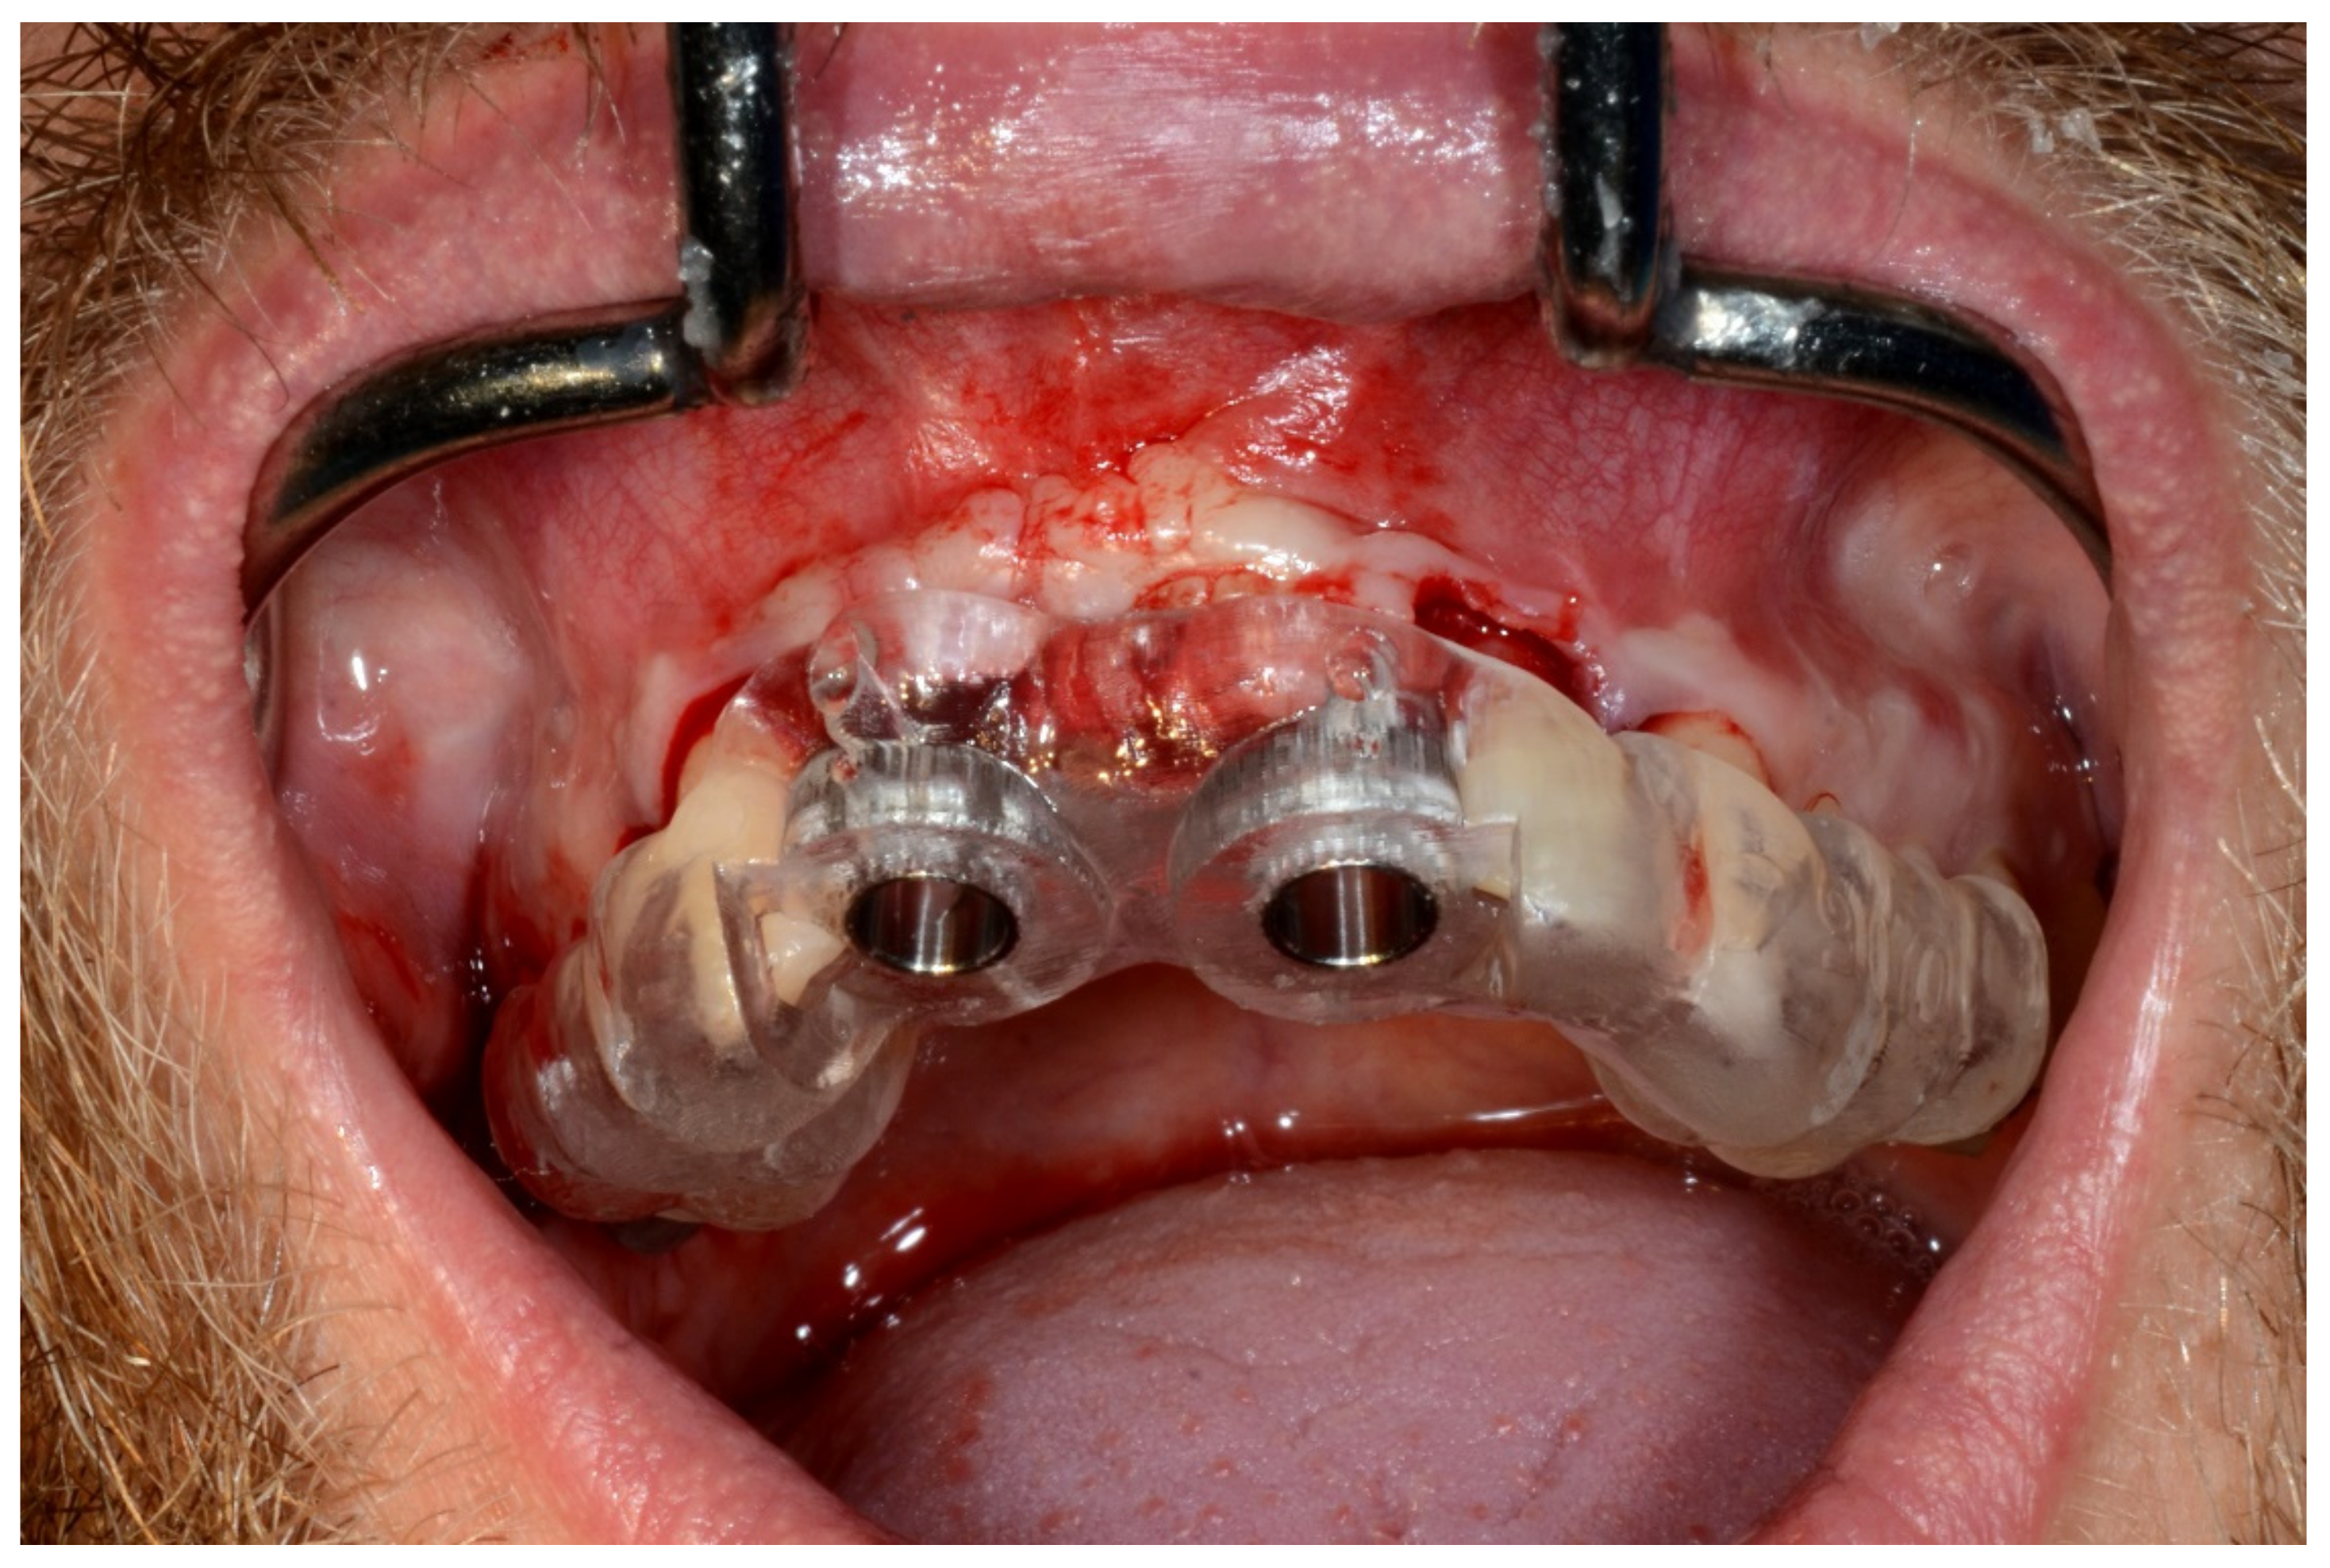

Figure 7.

Surgical drilling guides temporarily supported by teeth on the right and left sides.

In November 2017, two guided dental implants were placed at sites # 12 and # 21 (Figure 7, Figure 8, Figure 9, Figure 10 and Figure 11).